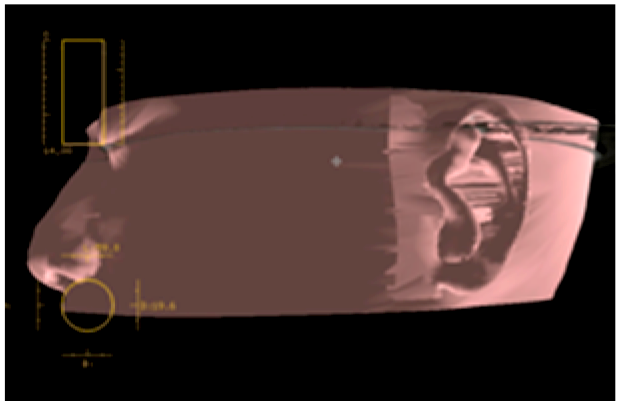

Figure 20. Navigation during drilling into the temporal bone. The drill (yellow bar) is guided to the expected position and direction (red rod).